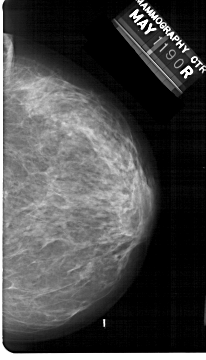

A_1303_1.RIGHT_CC

RIGHT_MLO LINES 5491 PIXELS_PER_LINE 3421 BITS_PER_PIXEL 12 RESOLUTION 43.5 NON_OVERLAY